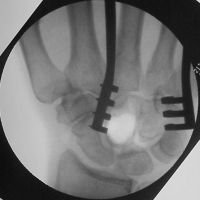

| Intraoperative

fluoroscopy of the defect after marginal excision with

a burr... |